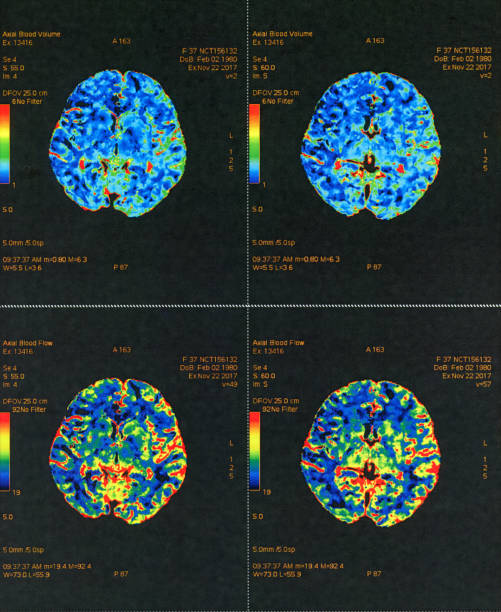

뇌 일부분에 혈액이 제대로 공급되지 않으면 혈관이 막히거나 터지기 때문에 뇌가 손상되며 여러 이상이 발생할 수 있는데 이러한 증상을 일컬어 뇌졸중이라고 합니다. 뇌졸중을 유발하는 원인에는 비만, 불규칙한 생활습관, 고혈압, 흡연 등으로 유발될 수 있으며 나타나는 전조증상들이 어쩌면 가볍게 넘길 수 있는 증상들이 많다보니 단순히 노화로 인한 증상으로 가볍게 여기는 경우도 있기 때문에 초기 대응이 어렵습니다. 따라서 이번 시간을 통하여 뇌졸중 전조증상에 대해 자세히 알아보고 초기 대응력을 높이시기 바랍니다.